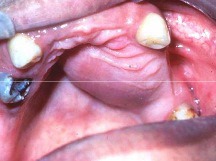

denture induced fibrous hyperplasia (epulis fissuatum)

-elongated folds of exophytic tissue surrounding denture flange in the vestibule -ill fitting denture